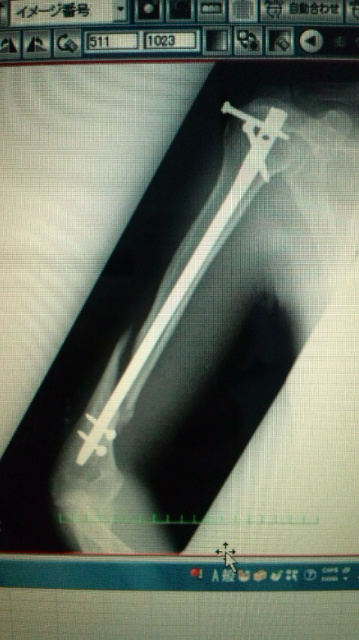

トントン後のレントゲンです。

くっついていません・・・残念・・・

ですが、筋肉の引きつりがなくなったので写りがくっきり綺麗になりました(^^)

(後に一番上のボルトを取りました。)